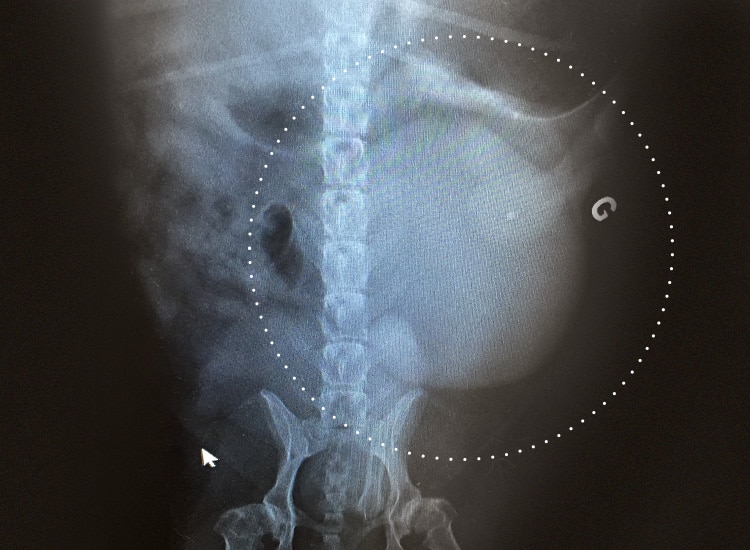

Le vétérinaire effectue une palpation et a recours à la radiographie et l’échographie afin de mettre en évidence une masse splénique au niveau de l’abdomen. Cependant il est également possible d’observer ce type d’image avec d’autres affections comme un hématome, par exemple, associé à une splénomégalie de la rate.

Radiographie mettant en évidence une tumeur de la rate chez un chien

Le vétérinaire procède à un diagnostic différentiel qui consiste à éliminer les affections dont les symptômes sont similaires à ceux de la tumeur splénique.